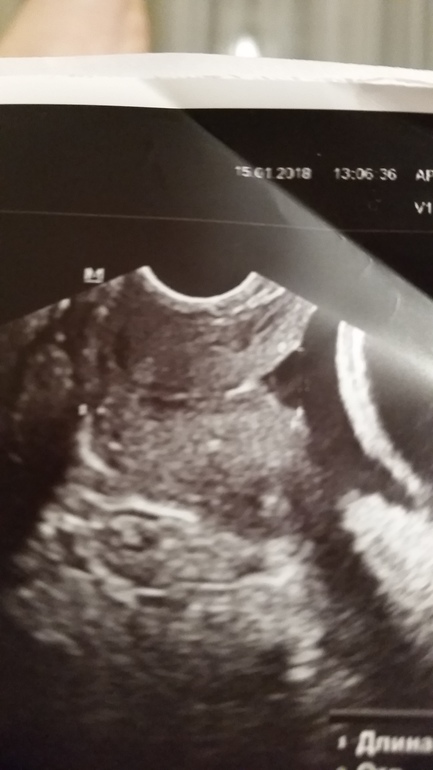

С 17 недель стоит пессарий. В 24 недели была воронка 17 на 10 мм, сохранная часть 24 мм. Тонуса не было, по-этому, ничего и не принимала. Пока хожу вот, все ок)) Вчера на осмотре сказали шейка закрыта, а длину не мерили уже очень давно. Совсем пластом не лежала, просто не напрягаюсь, много отдыхаю. Думаю, недельки 2-3 точно прохожу, а может и до пдр. Мне кажется, если тонуса нет, то зачем в себя лишние медикаменты впихивать. Да, все это время я на утрожестане вагинально. Было 600, сейчас плавно снижаю и к 36 неделям полностью отменю

У меня в дневнике есть фото с узи с воронкой